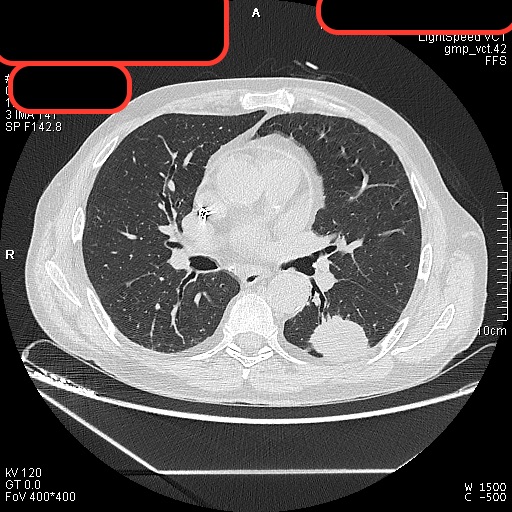

Las características de la masas se estudian mejor mediante la TC. Nos va a permitir definir el tamaño, la morfología, la posición, los bordes, cavitaciones, calcificaciones, etc para propiciar un buen diagnóstico. Además la TC es capaz de detectar nódulos y masa que no aparecen en la Rx de tórax, adenopatías mediastínicas, lesiones extraparenquimatosas y ayuda en la planificación de la biopsia o de la punción del nódulo. La TC se solicita también para valorar la respuesta al tratamiento y la progresión de la enfermedad.